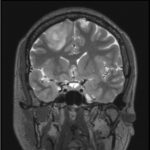

- 頭CT検査や頭MRI検査で見つかることが多く、画像検査のみでおおよそ診断できることが多いです。

- 腫瘍の代謝情報を得るためにメチオニンPET検査を行うことがあります。